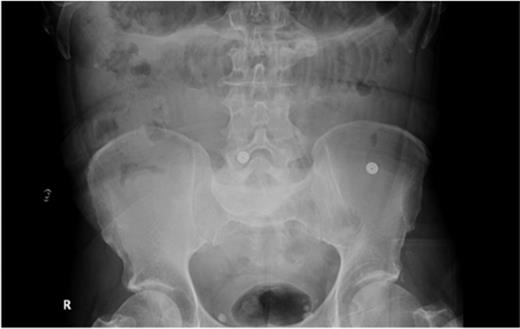

Laboratory investigations revealed an International Normalized Ratio (INR) of 10; she was anticoagulated with warfarin due to her atrial fibrillation. Initial imaging revealed dilated small-bowel loops on abdominal radiograph (Fig. 1).

Abdominal radiograph showing dilated small-bowel loops (Case 1).